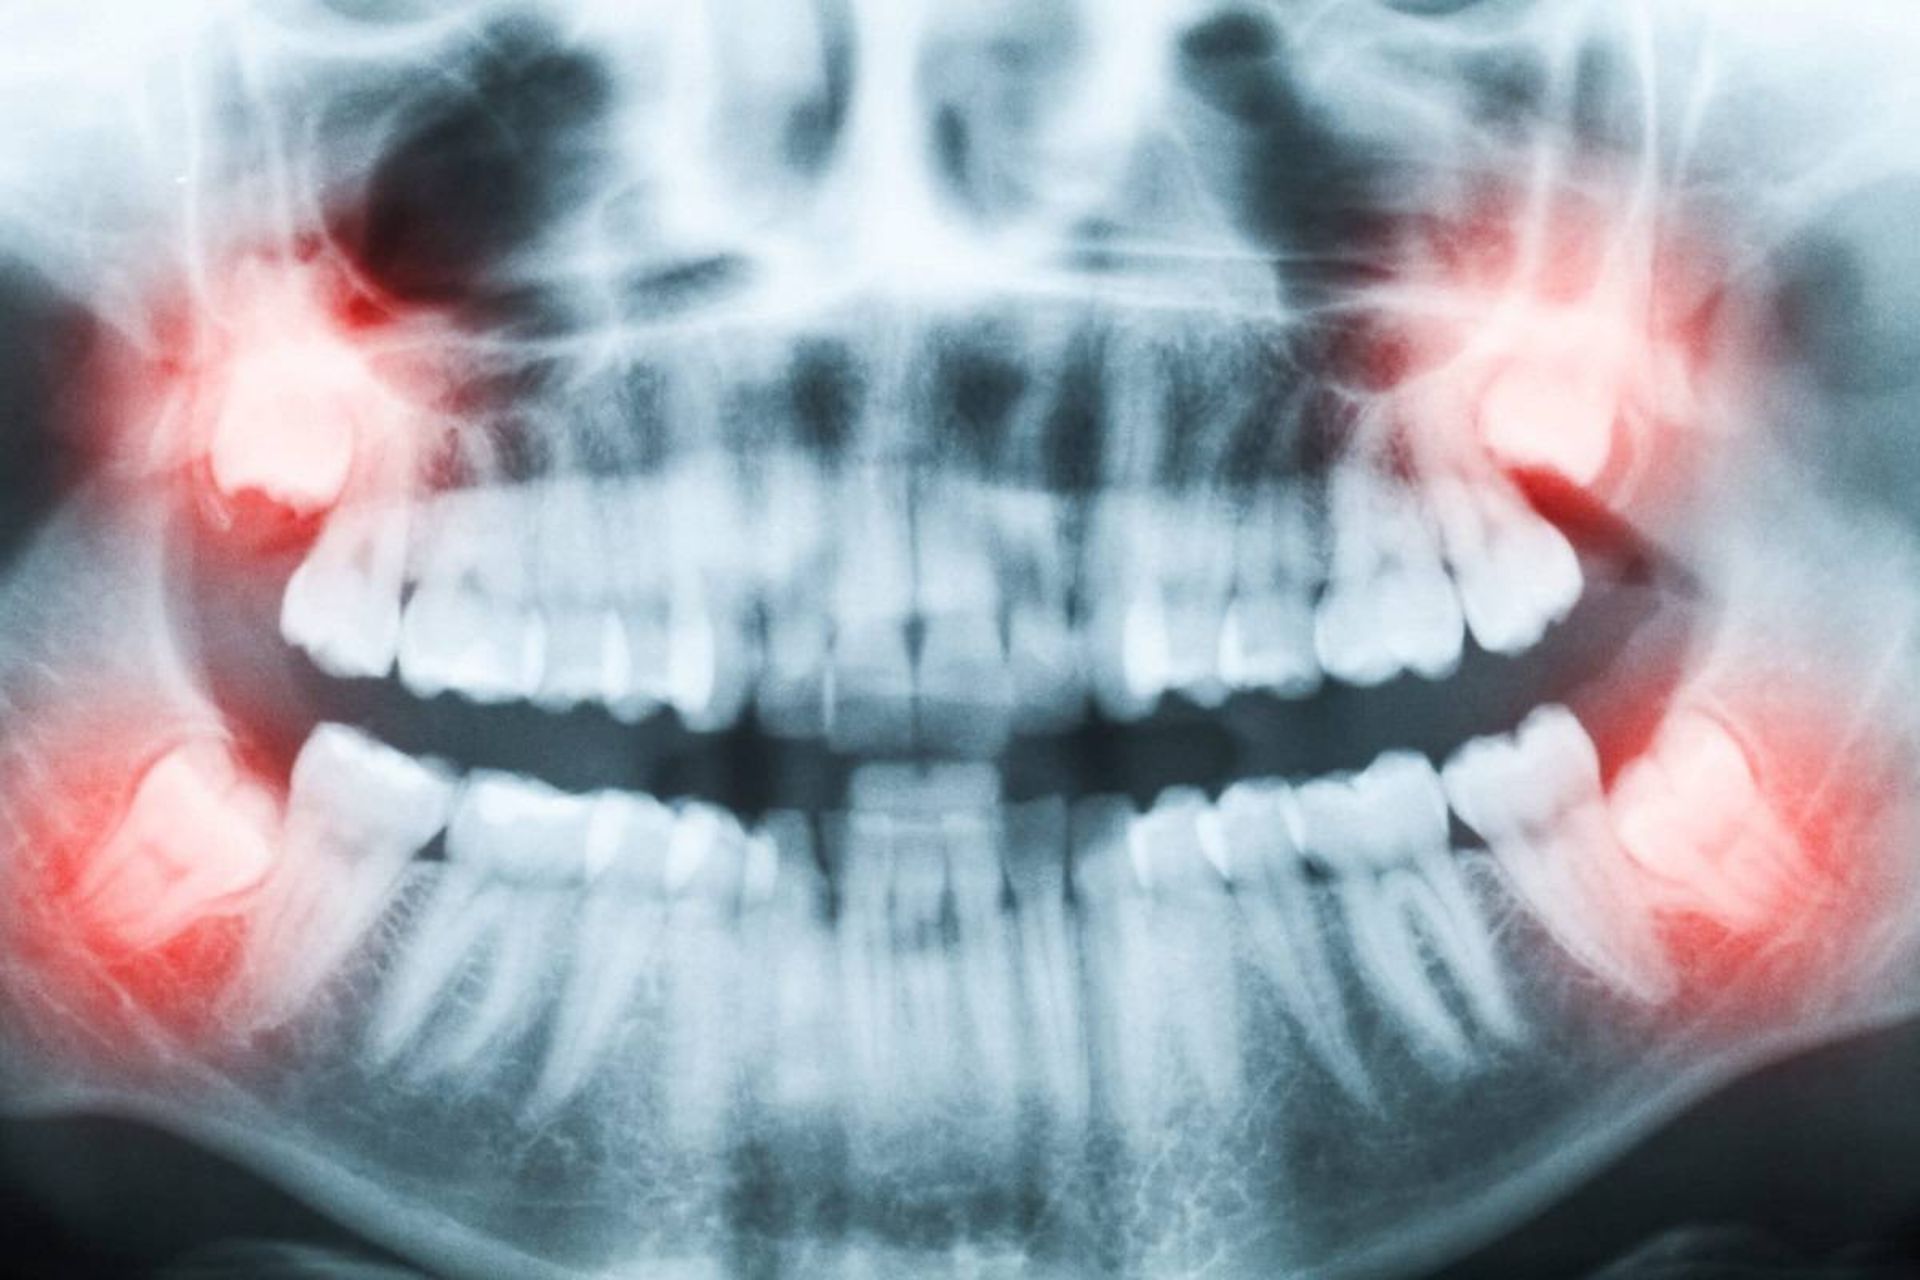

دندان‌های عقل بسیار دیر می‌رویند، اما علت این موضوع چیست و آیا این دندان‌ها هرگز برای انسان‌ها مفید بوده است؟

کشیدن دندان‌های عقل برای بسیاری از افراد در اواخر نوجوانی و اوایل دهه سوم زندگی مرسوم است. اما چرا این دندان‌ها در دوران کودکی همراه بقیه دندان‌های دائمی ما درنمی‌آیند؟

پاسخ به رشد کودک ارتباط دارد. در فک کودک فضای کافی برای رشد دندان‌های عقل وجود ندارد. اما همگام با رشد کودک، فک او نیز بزرگ می‌شود و فضایی برای رویش دندان‌های عقل مهیا می‌شود. اگرچه در بیشتر موارد، فک‌ انسان‌های مدرن به‌اندازه‌ی کافی بزرگ نمی‌شود که دندان‌های عقل بتوانند بدون مشکل رشد کنند. به‌همین‌دلیل، است که کشیدن دندان‌های عقل رایج است.

امروزه، دندانپزشکان اغلب دندان‌های عقل را خارج می‌کنند، زیرا رویش آن‌ها می‌تواند موجب درد در دهان شلوغ شود. حتی اگر فردی درد نداشته باشد، خارج کردن دندان‌های عقل در جوانی می‌تواند از مشکلات سلامتی بعدی مانند عفونت لثه پیشگیری کند.